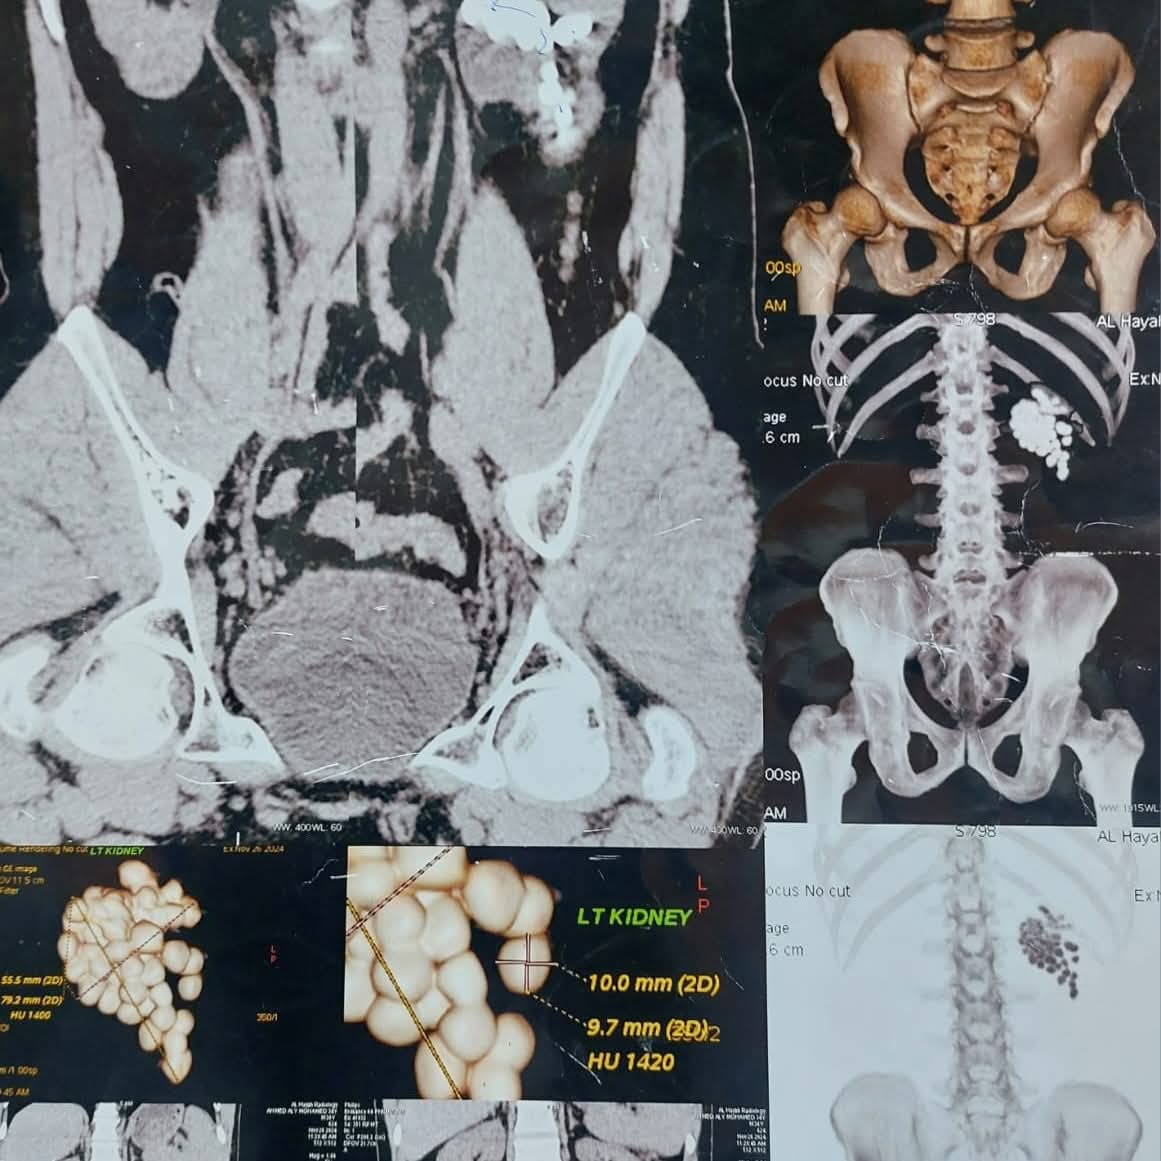

نجح فريق طبي متخصص ، بمستشفى المعبر الجامعي بقنا ، في إجراء عملية دقيقة لاستخراج 58 حصوة من الكلية اليسرى لمريض يبلغ من العمر 40 عامًا، وذلك باستخدام أحدث تقنيات مناظير الكلى المتقدمة.

وأوضح الدكتور مصطفى عبد الرازق ، رئيس قسم المسالك البولية، أن المريض وصل وهو يعاني من آلام متكررة وارتفاع في نسبة الأملاح، وبفحصه تبيّن وجود عدد كبير من الحصوات المتجمعة في حوض الكلية اليسرى، ما استدعى التدخل الجراحي حفاظًا على وظائف الكلية.

وأشار عبد الرازق، إلى أنه تم تجهيز المريض وإخضاعه للتخدير العام، ثم البدء في العملية من خلال فتحة صغيرة لا تتجاوز سنتيمترًا واحدًا للوصول إلى الكلية، قبل تفتيت الحصوات باستخدام تقنيات التفتيت الهوائي والليزر تبعًا لطبيعة كل حصوة.

واستمرت العملية نحو ساعتين، تمكن خلالها الفريق الطبي من إزالة جميع الحصوات والتأكد من تنظيف حوض الكلية بالكامل، مع تركيب أنبوب تصريف مؤقت لضمان خروج السوائل بصورة آمنة.، وخرج المريض من غرفة العمليات في حالة مستقرة، وتمت متابعته داخل الإفاقة وسط تحسن ملحوظ في حالته ووظائف الكلى.